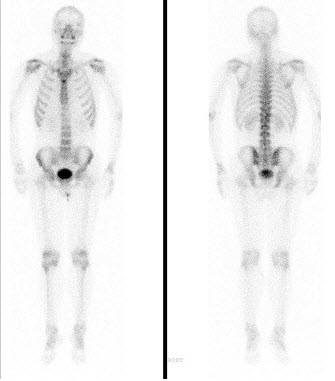

163、多项选择题

男性,67岁,阵发性心前区疼痛2年,心电图运动试验阳性,行Tc-MIBI运动-静息心肌显像如图,可能的诊断是()

A.左室前壁、下壁可逆性缺血

B.冠状动脉粥样硬化性心脏病

C.如果冠造阴性,提示X综合征

D.不排除非粥样硬化型冠心病

E.未见心肌缺血

点击查看答案